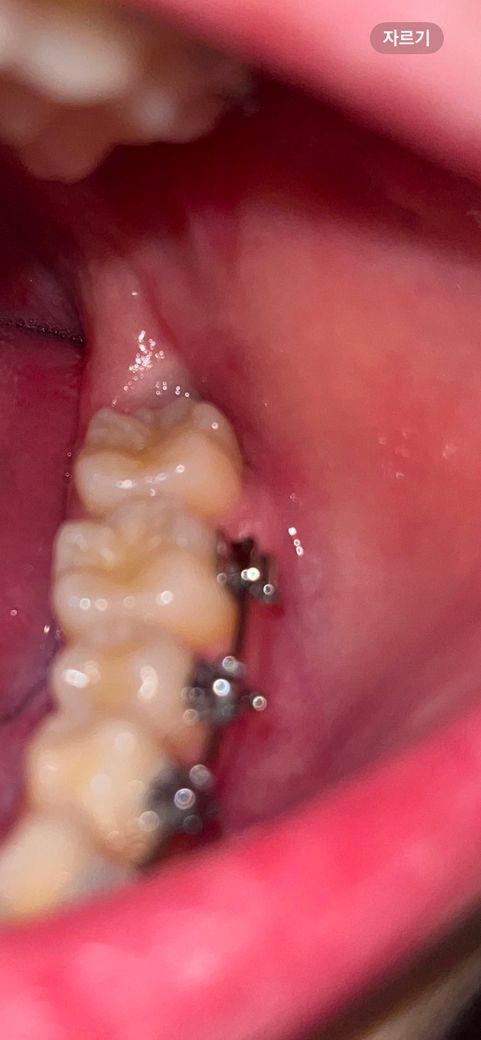

매복 사랑니 발치한지 3주째 통증있을수있나요?

매복사랑니 발치한지 3주째 되는데요. 아직 통증이있을 수 있나요? 가만히 있을땐 안아픈데 발치한 잇몸 뼈쪽을 누르거나 만지면 아파요 발치한 쪽으로 입꼬리를 올려도 좀 아파요… 정상인가요?.. 음식물 관리도 주사기로 하는데 안빠지는 음식물이 있을까봐 불안하네요…사진상 잘나아가고있나요?

이정도면 정상적으로 아물고 있는 것으로 보입니다. 원래부터 사랑니 뽑은 자리는 몇달에 걸쳐 스스히 완전히 아뭅니다. 음식물이 끼여도 큰문제 되지 않고 저절로 빠져 나오니 주사기로 일부러 빼지 않아도 됩니다.

사진에서는 발치부위가 가려 정확히 보이진 않으나 치유는 어느정도 된 것 같아 보입니다 통증은 지속된다면 사랑니 뺀 치과를 힌번 가보시기 바랍니다